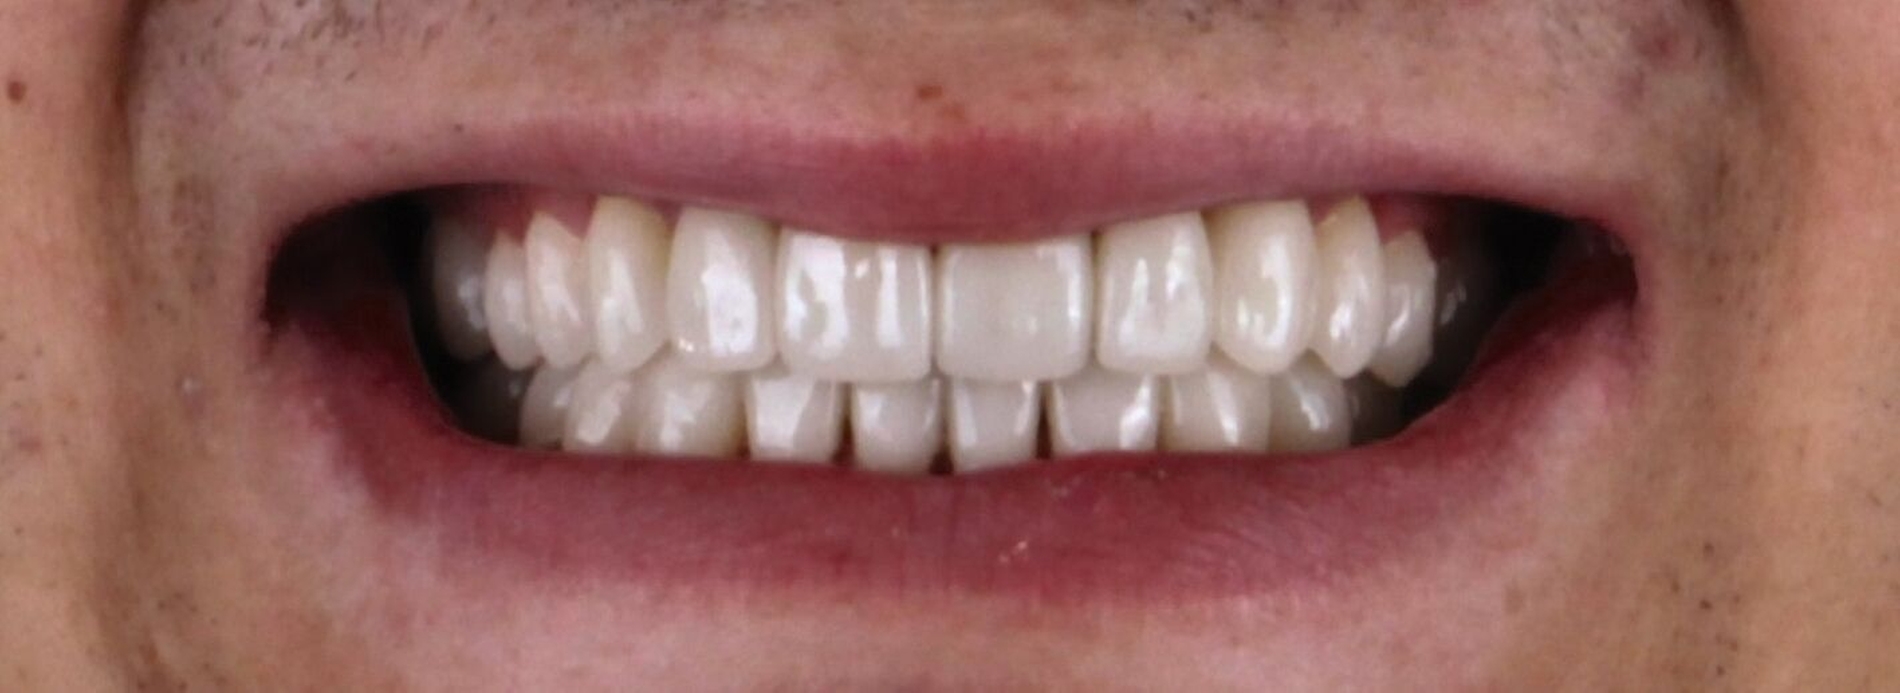

Zu Beginn wurden mit Alginat Abformungen der Ausgangslage genommen. Anhand der Situationsmodelle konnten mithilfe einer Modellanalyse nach dem Udo-Plaster-Protokoll [Plaster und Köttgen, 2020] Rückschlüsse auf einen vertikalen Höhenverlust von etwa 3 - 4 mm gezogen werden. Für die Registrierung der neuen Höhe wurde der Patient mit einer temporären Einweg-Schiene (Aqualizer®, MediPlus GmbH, Unterleinleiter) deprogrammiert. Anschließend wurde am stehenden Patienten ein Bis-Acrylat-basierter Frontzahn-Jig (LuxaBite, DMG, Hamburg) angefertigt, so dass die Bissnahme als vorläufige patientenindividuelle Myozentrikposition reproduzierbar im Seitenzahnbereich mit einem A-Silikon (Kanibite hart, Kaniedenta, Herford) erfolgen konnte. Basierend auf dieser Höhe wurde eine Bisserhöhungsschiene angefertigt, die der Patient über sechs Monate lang trug. Nach einem Intraoralscan des Ober- und Unterkiefers (Primescan, Dentsply Sirona, Bensheim) konnte ein digitales Wax-up erstellt werden. Auf den 3-D-gedruckten Wax-up-Modellen wurde ein Silikonschlüssel für die Mock-up-Versorgung hergestellt und mit einem Bis-Acrylat-Komposit (Luxatemp Star, DMG, Hamburg) umgesetzt.

Da der Patient mit der Situation zufrieden war, konnte nach einigen Wochen die endgültige Versorgung bestehend aus Lithiumdisilikat-Kronen (e.max®, Ivoclar, Schaan, Liechtenstein) adhäsiv mit einem dualhärtenden Befestigungskomposit (RelyXUltimate™, 3M™, Neuss) eingesetzt werden. Der Patient bekam außerdem eine Unterkiefer-Aufbissschiene mit adjustierter Kaufläche für die Nacht.

Der Patient konnte vollständig saniert werden und kam mit der neu eingestellten Bisshöhe sehr gut zurecht. Während der Behandlung wurden Ernährungshinweise gegeben, um die langfristige Haltbarkeit der Restauration zu gewährleisten. Eine besondere Herausforderung stellten in diesem Fall der angestrebte Ausgleich der verlorenen vertikalen Höhe und die Bestimmung der Myozentrikposition dar.